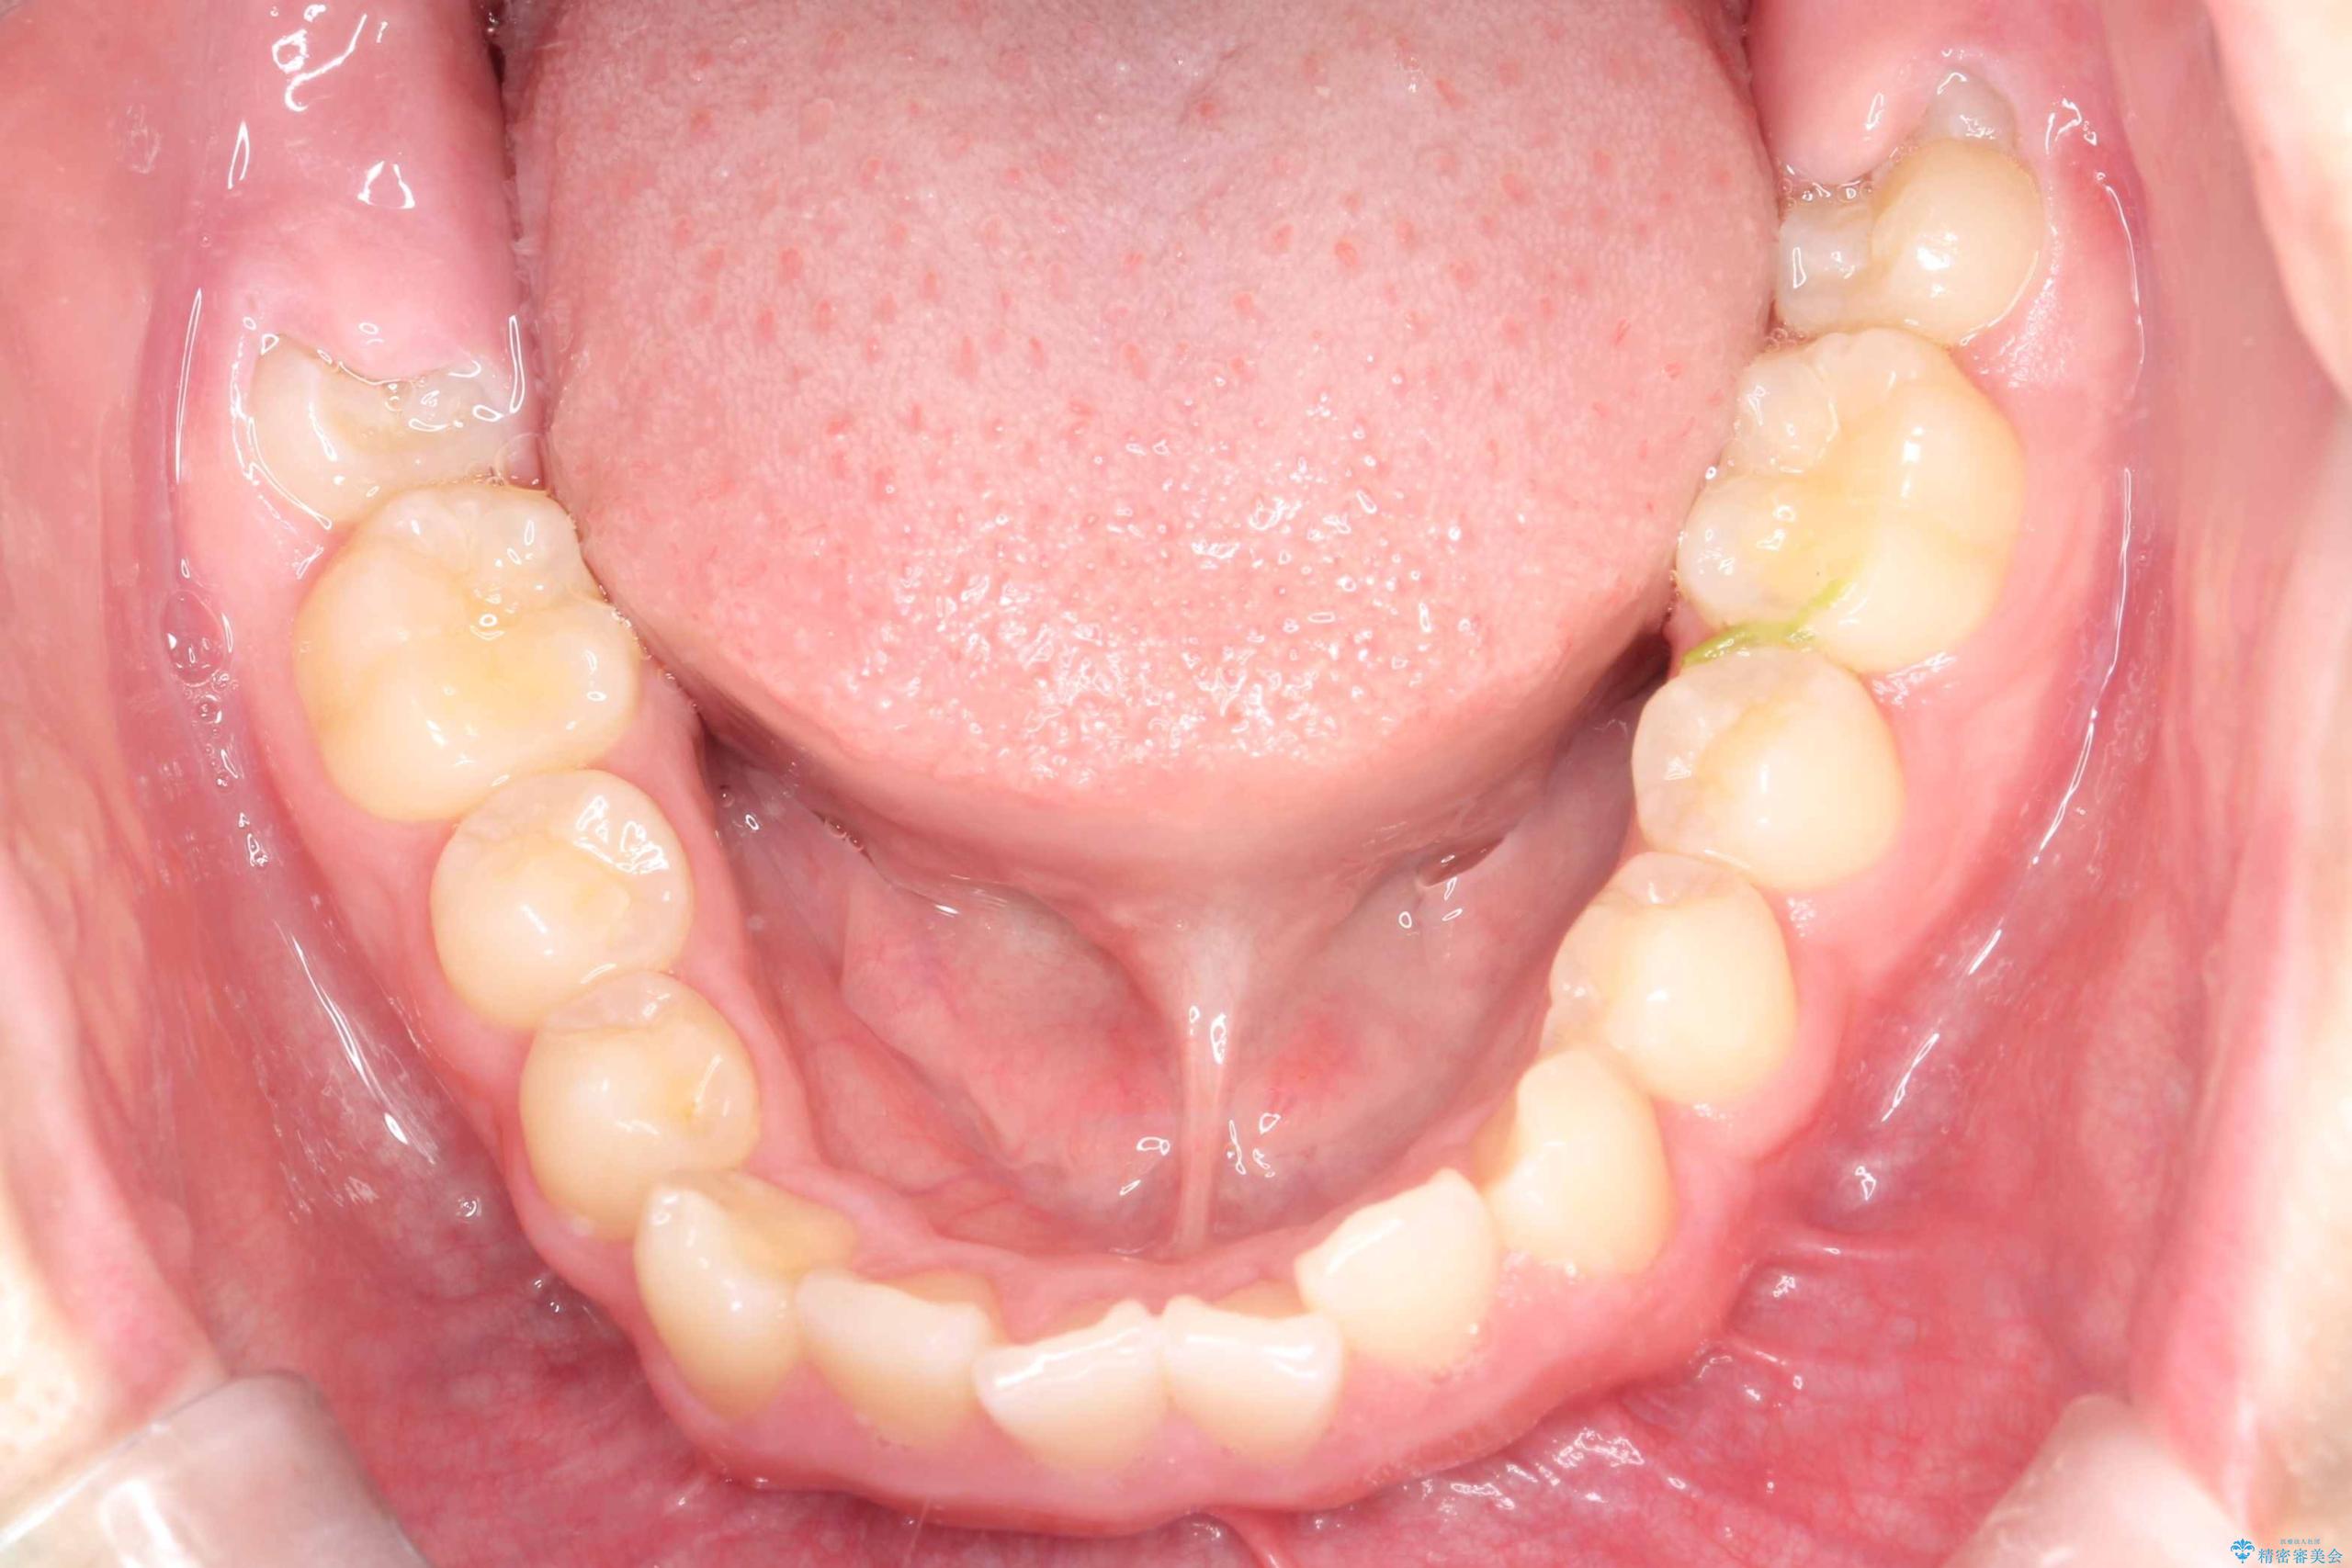

八重歯・歯並びのデコボコとディープバイトを改善した抜歯ワイヤー矯正症例

- 八重歯と咬み合わせを治したいを主訴にご来院された患者様です。

矯正の精密検査の結果上顎左右4番の計2本を抜歯し、審美性に配慮したワイヤー矯正装置(審美装置)を用いて治療を行いました。

八重歯などの歯列のデコボコが綺麗に改善され、患者様にも大変喜んでいただけました。また、咬み合わせが深い「ディープバイト」も併せて改善し、見た目だけでなく機能面でもバランスの取れた咬合を獲得しています。